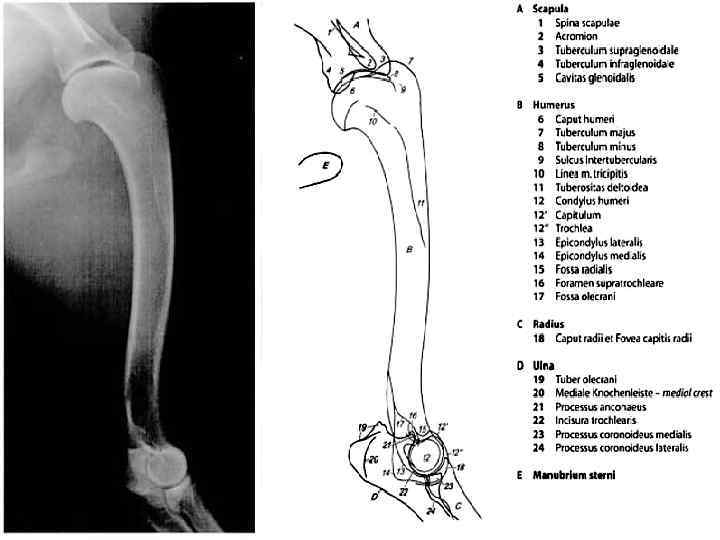

РЕНТГЕНОАНАТОМИЯ СУСТАВОВ

Рентген/КТ !!! Укладки ? ? ?